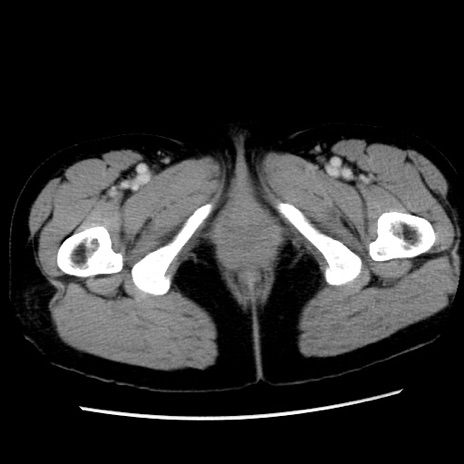

矢状断像

【症例】 50歳代女性

【主訴】 腹痛

【現病歴】前日生レバーを食べた。今朝に排便あり。 昼前に突然発症の腹痛を生じ、当院救急外来を受診した。

【身体所見】 意識清明、腹部:平坦、軟、下腹部やや左を中心に圧痛・反跳痛あり、筋性防御あり